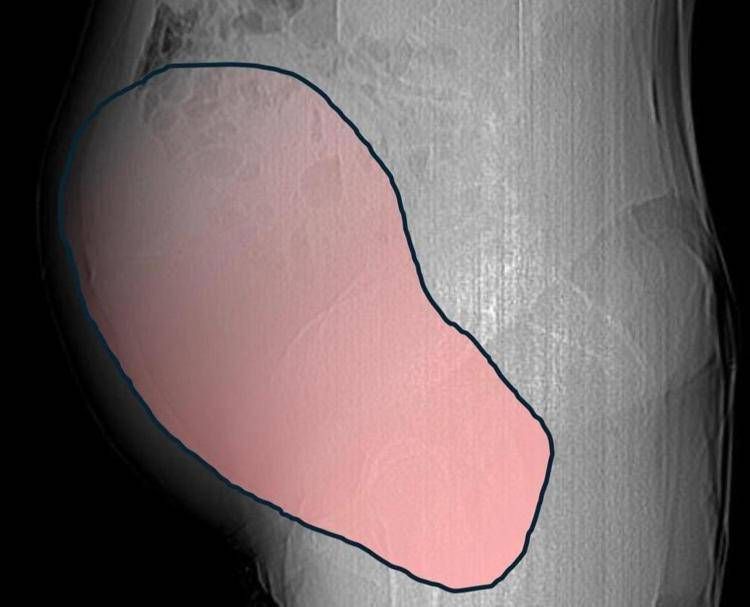

Una donna di 69 anni è stata salvata grazie a un intervento chirurgico complesso di sei ore, effettuato presso l’ospedale Sant’Anna di Torino. La paziente si è presentata al pronto soccorso a metà dicembre 2025, quando ha iniziato a manifestare sintomi gravi a causa di un tumore ovarico di dimensioni straordinarie. Questa neoplasia, con un diametro di circa 28 centimetri e un peso di circa 6 chilogrammi, era rimasta asintomatica per lungo tempo, fino a quando non ha cominciato a comprimere il colon, causando difficoltà intestinali acute.

La donna ha scoperto la presenza della cisti solo quando il suo corpo ha iniziato a dare segnali di allerta. L’ospedale Sant’Anna ha comunicato che la massa ovarica, associata a una seconda neoplasia intestinale, ha causato un’emergenza medica. La paziente ha riferito di sintomi che non potevano più essere ignorati, portandola a cercare assistenza medica. Il team della Chirurgia Ginecologica Mininvasiva, guidato dal dottor Paolo Petruzzelli, ha preso in carico il caso con urgenza, considerando anche l’imminente arrivo delle festività natalizie.

Il 23 dicembre, a poche ore dalla vigilia di Natale, la paziente è stata sottoposta a un intervento chirurgico. La complessità dell’operazione è emersa durante la procedura, quando i medici hanno constatato la gravità della situazione. Hanno dovuto affrontare non solo la rimozione della neoplasia ovarica, ma anche la gestione della sofferenza intestinale. Il lavoro di squadra tra ginecologi oncologi, chirurghi, anestesisti e altri specialisti è stato cruciale per il successo dell’intervento.